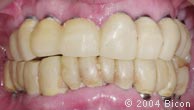

99. |

抛光后的临时义齿。 |